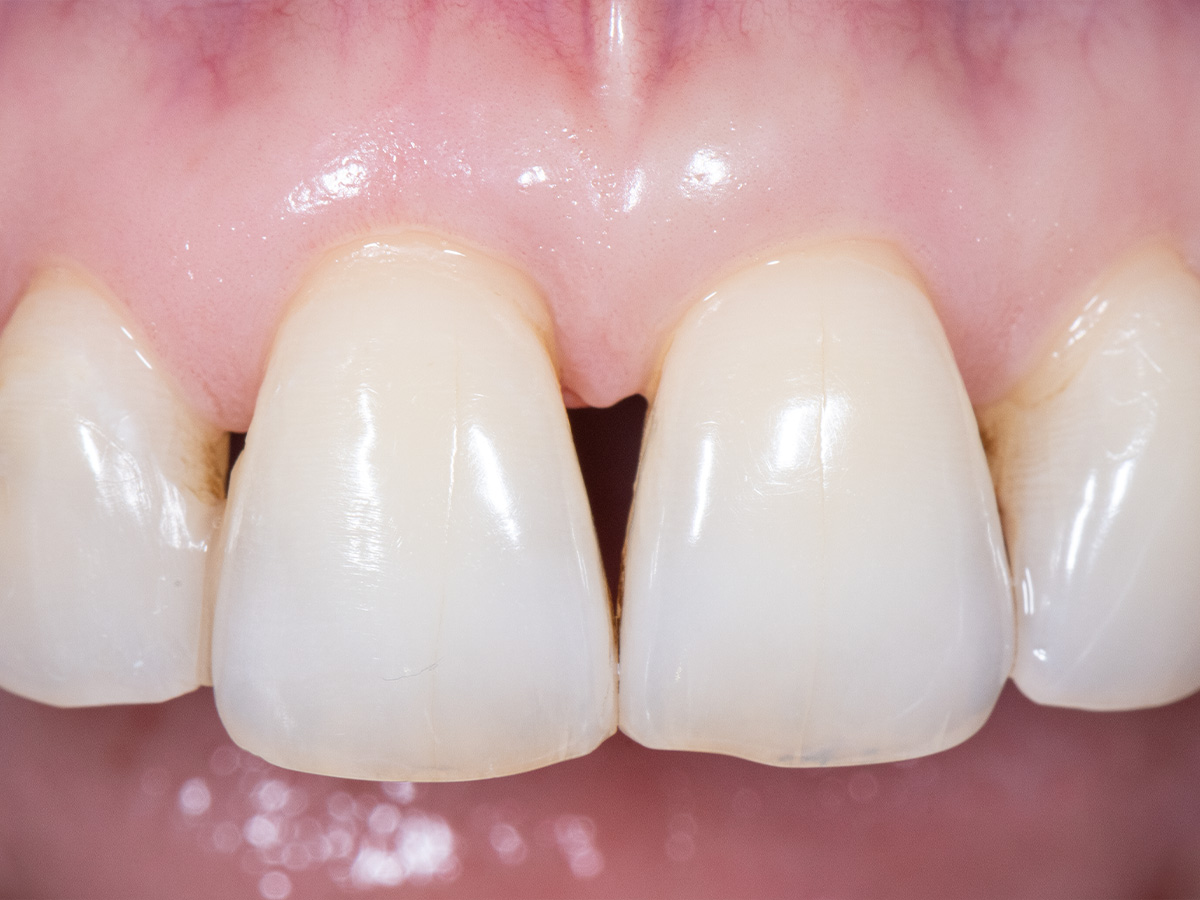

Die klinische Untersuchung nach sechs Monaten zeigt einen parodontal gesunden Zustand, keine Gingivarezession und keine Narbenbildung, da Oberflächeninzisionen auf der bukkalen Seite vollständig vermieden wurden

Abbildung 11

Abbildung 12

Das finale Bild nach Verschluss des Interdentalraumes mittels direkter Kompositrestaurationen zeigt ein ästhetisch ansprechendes Ergebnis.